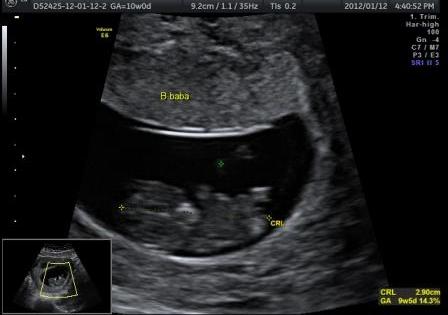

Én ma voltam UH-on és már 15,3 mm-es a drágaságunk.